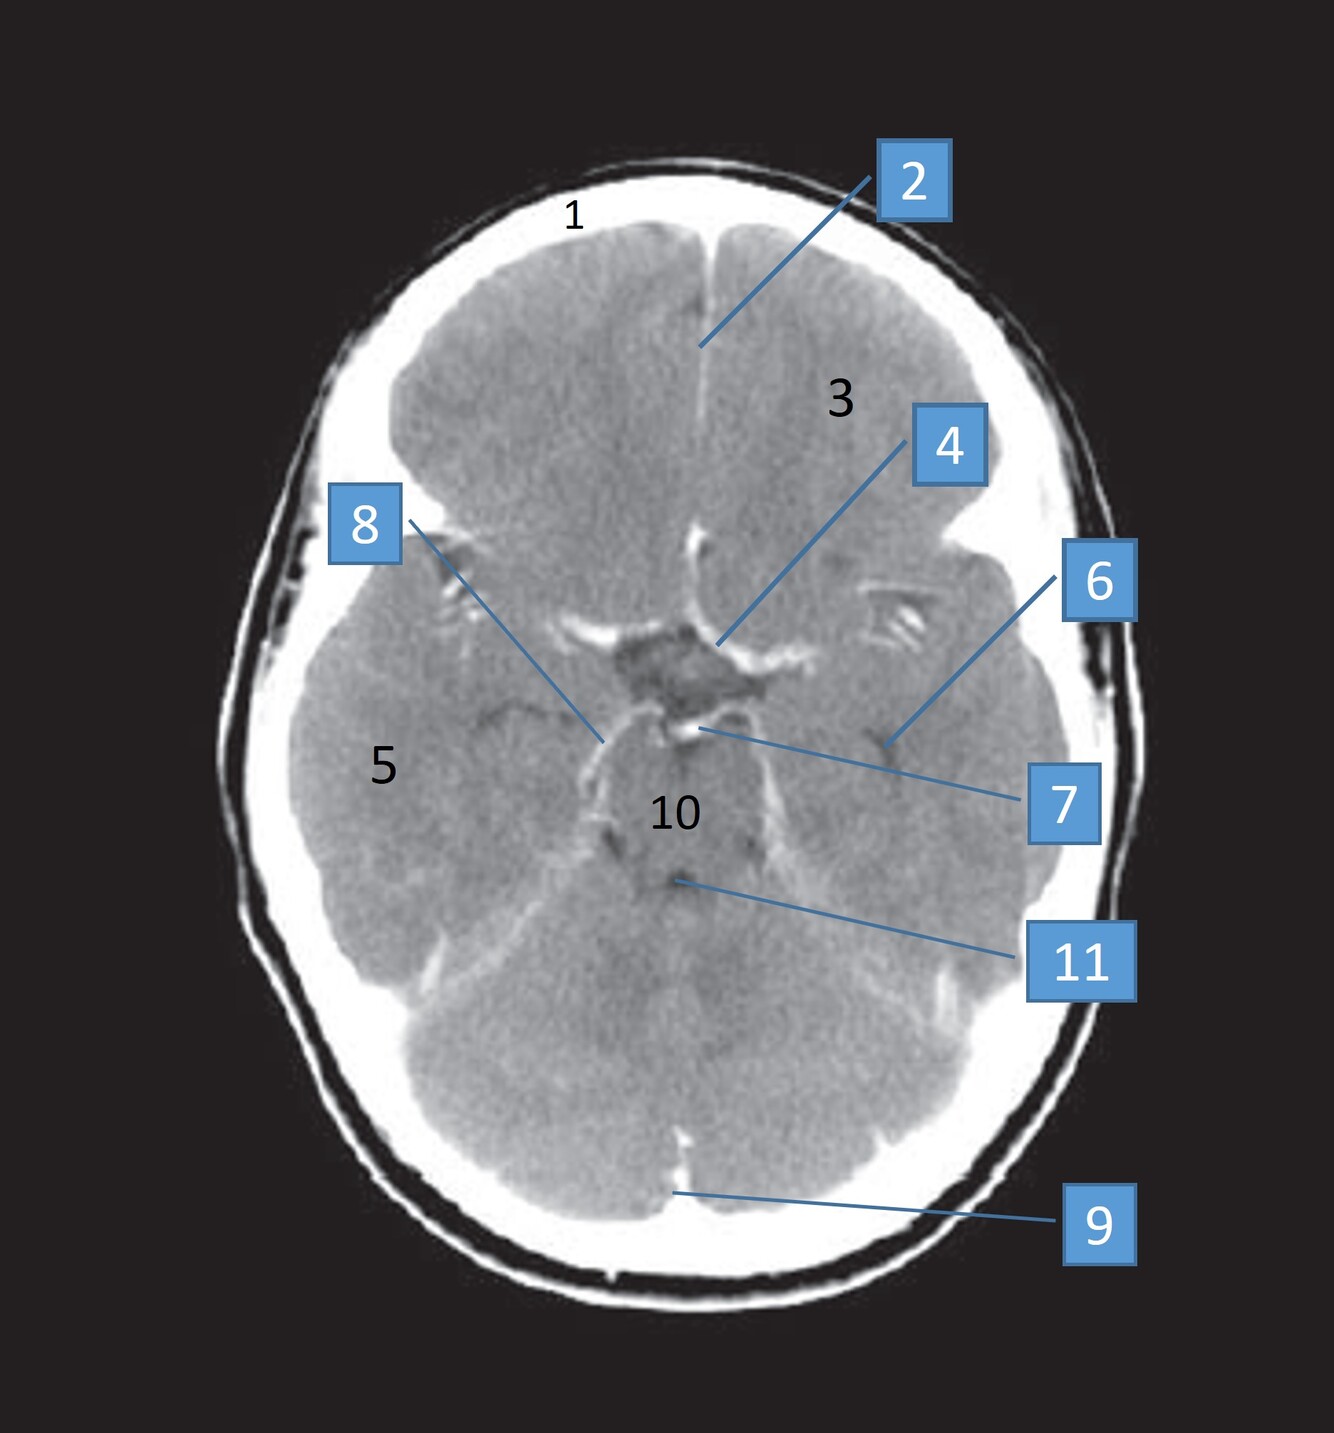

Label 2,3,4,5,7,8

2=Rt Caudate nucleus

3=Corpus callosum

4=Lt lateral ventricle

5=Third ventricle

7= Septum Pellucidum

8= Rt Interventricular foramen